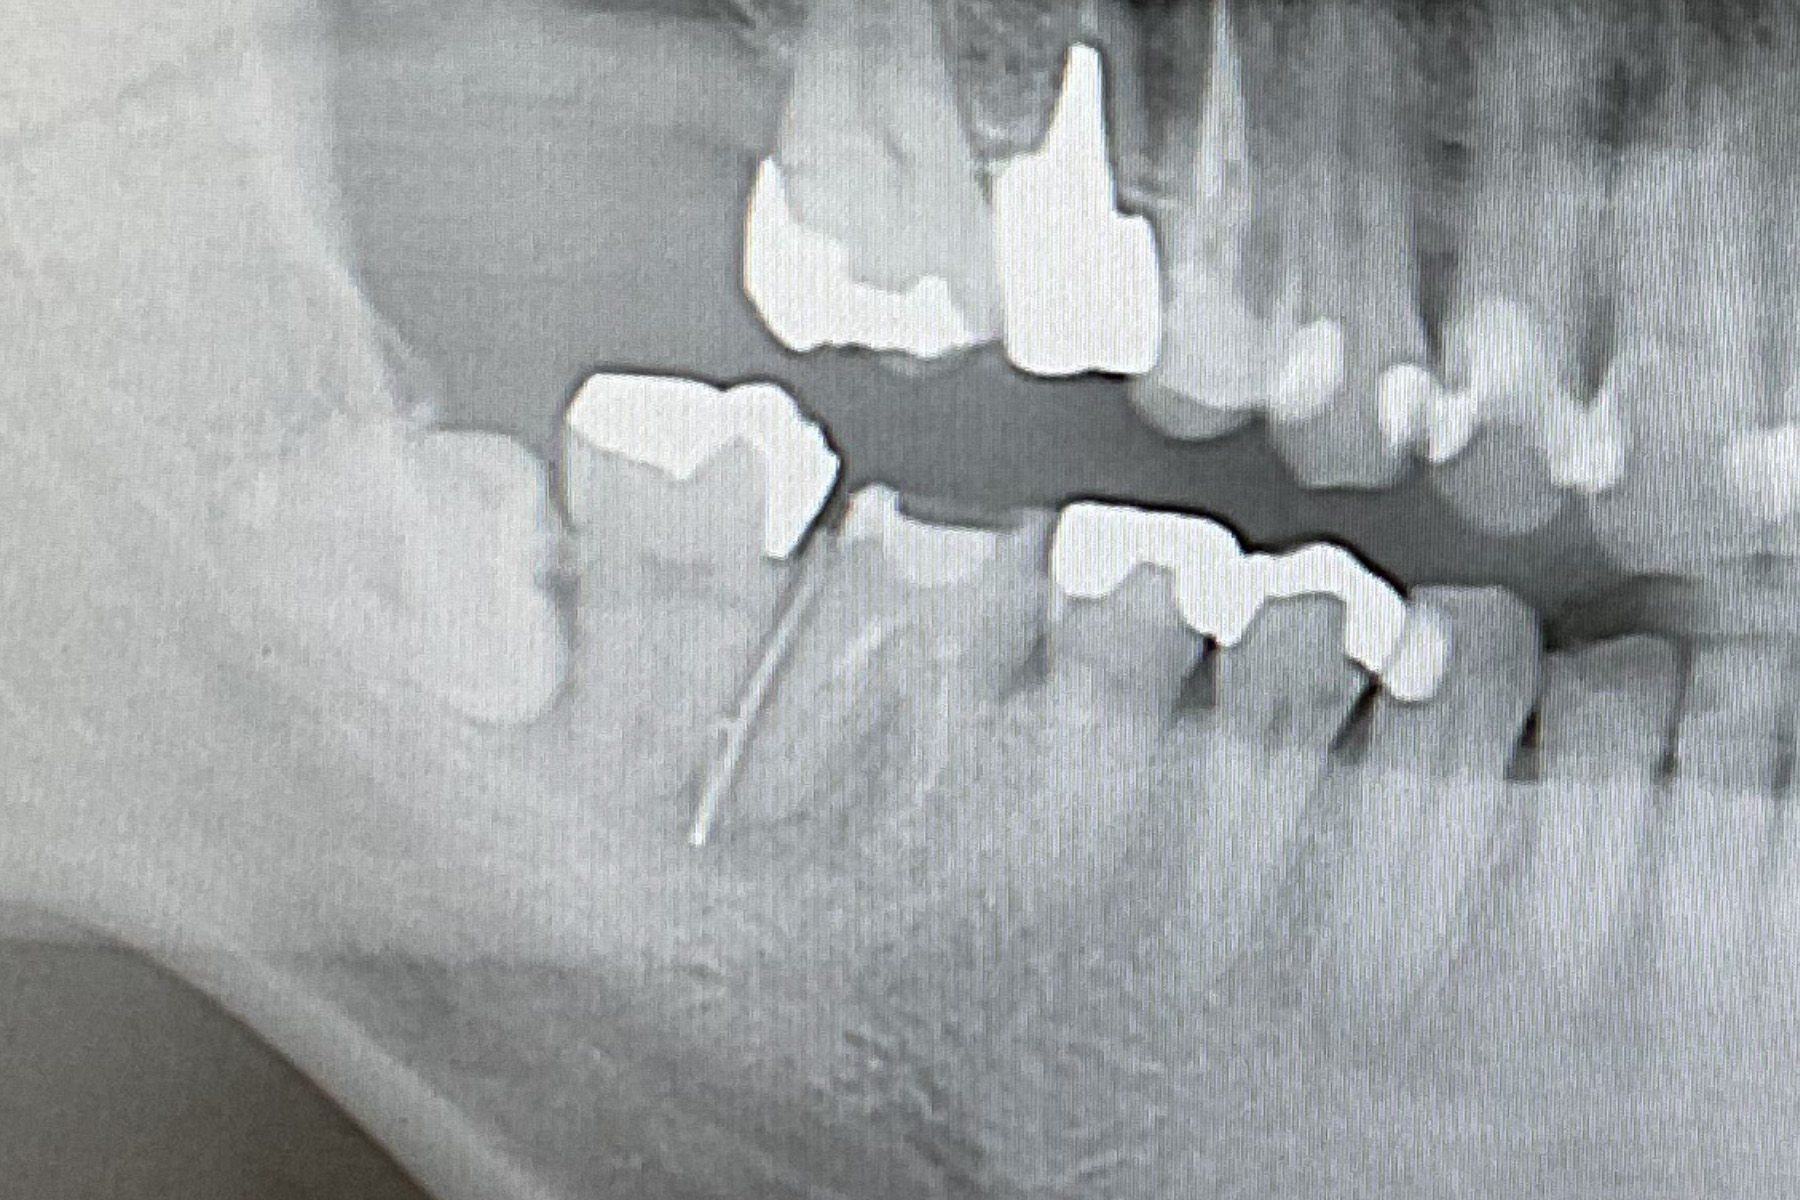

implant-case02-bf1